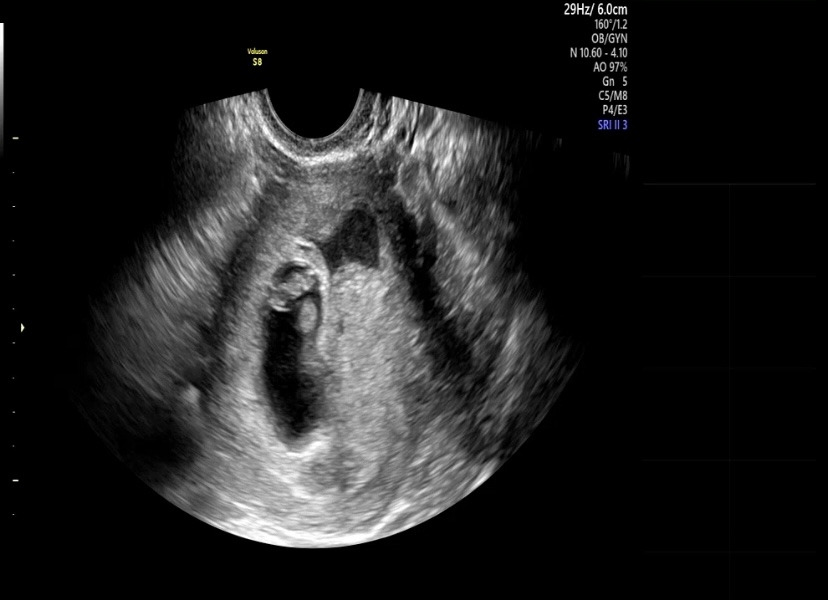

그새 아기집도 많이 커졌다. 아내 앞에서 우리 아기가 뚝딱뚝딱하며 집을 넓히고 있지 않을까 하며 망치질하는 시늉을 하며 같이 웃곤 했다. 튼튼하게 집을 지어줘. 바람이 불어도 날아가지 않게.